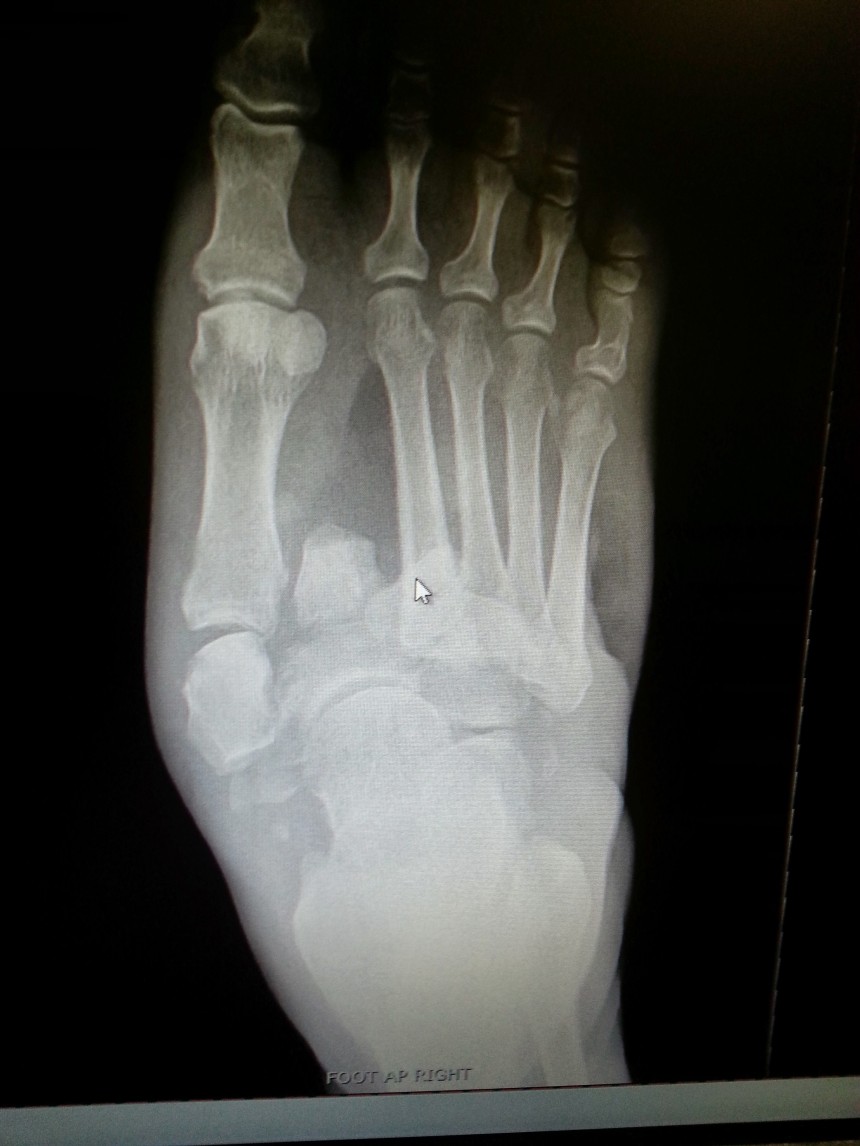

Charcot foot Image Can Charcot Foot Come Back But some things can trigger it: Charcot foot ranges in severity, and damage can be permanent. Who will look after my foot?. There’s no specific cause for charcot foot. This condition is also called charcot neuroarthropathy, charcot arthropathy, or diabetic foot. Can develop charcot foot in both feet. Your foot may become deformed if you do not get appropriate treatment. Can Charcot Foot Come Back.

From radiopaedia.org

Can Charcot Foot Come Back . There’s no specific cause for charcot foot. For those with an active charcot foot, this means that fractures and dislocations can occur without a whisper of pain, silently and progressively altering the foot and ankle. Your foot may become deformed if you do not get appropriate treatment early enough and you. Can develop charcot foot in both feet. Charcot foot ranges in severity, and damage can be permanent. Early diagnosis is critical for avoiding surgery, including amputation. This condition is also called charcot neuroarthropathy, charcot arthropathy, or diabetic foot. But some things can trigger it: Charcot foot is a condition that can develop from peripheral neuropathy caused by diabetes. Charcot foot, a serious complication of diabetes, is a condition that affects the bones, joints, and soft tissues of the foot. Who will look after my foot?. The chronic charcot foot — a ‘rocker bottom’ foot caused by dislocation and fracture of the bones in the midfoot. A sprain or broken bone that doesn’t get.